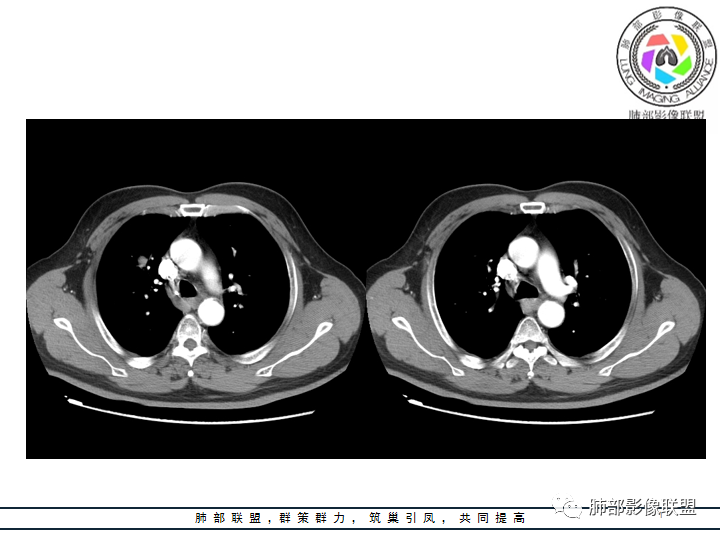

老年男性患者,长期吸烟史,没有呼吸系统临床表现。胸部CT示右肺上叶实性密度结节影,密度均匀,未见空洞及钙化,边缘较光整,未见分叶及毛刺。血管影旁现侧出,支气管进入并截断,不均匀强化。

郑昊宇:老年男性 右肺结节 ,考虑肿瘤性病变,影像关键是判断是否有支气管进入,需要薄层和重建,如果进入,明显强化,考虑类癌可能,如果没进入,考虑psp。

王飞:这里可见支气管阻塞中断,神经内分泌能性大于PSP。

刘海玲:右肺上叶实性结节,边缘有分叶,增强后有强化。考虑恶性,腺癌可能。